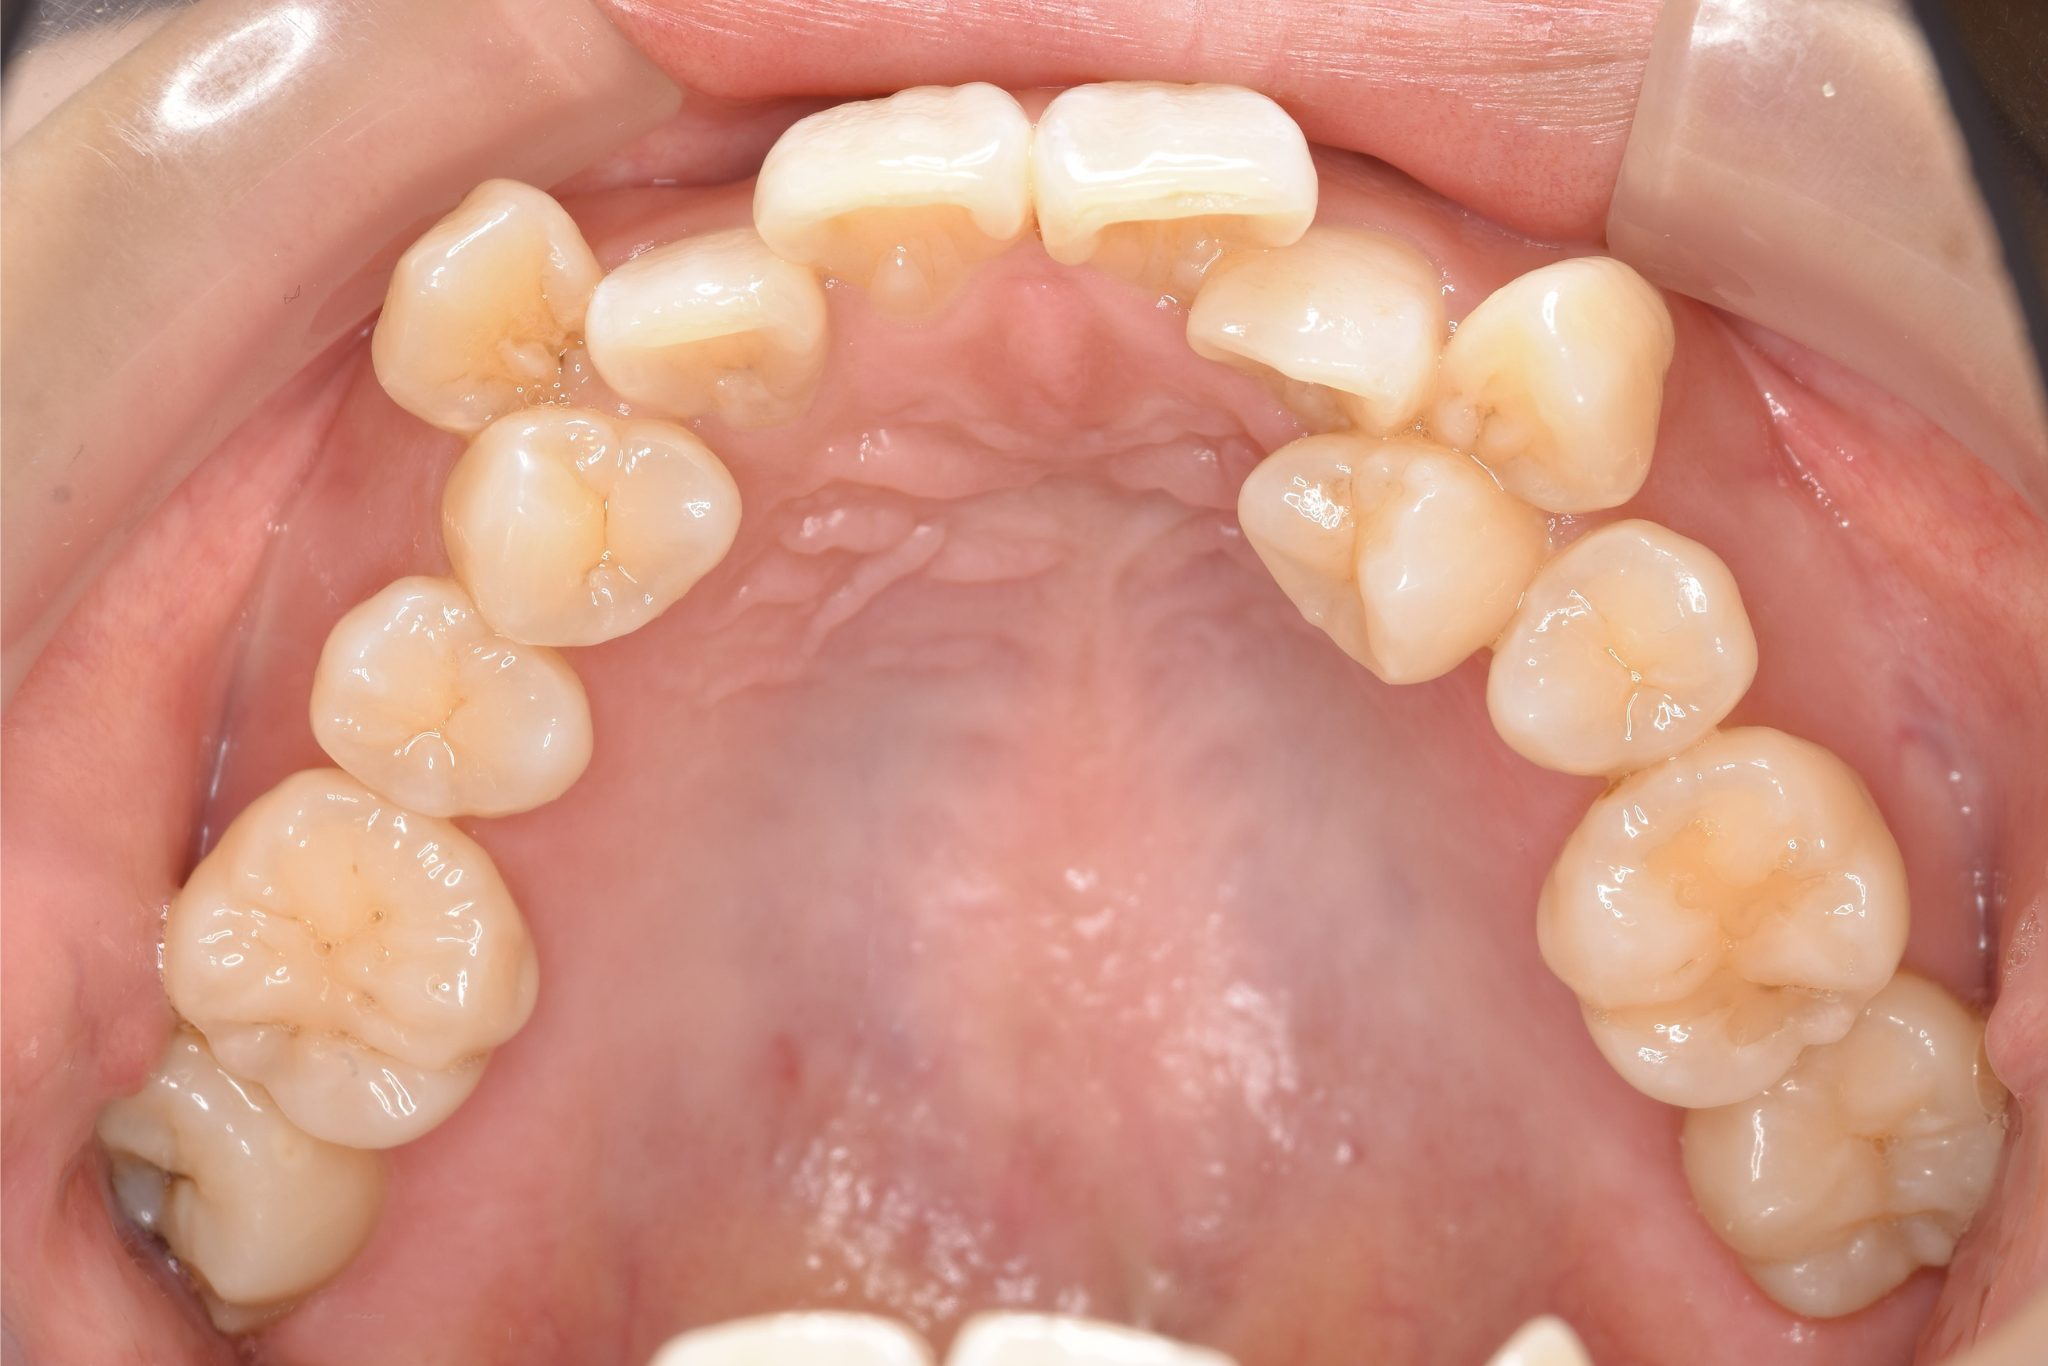

アフター

ワイヤー矯正治療|症例_814

施術内容 MSEと下顎リンガルアーチを用いて上下顎骨を拡大した。

その後上顎3・4番を抜歯しマルチブラケット装置とミニインプラントを用いて

歯牙を配列した。良好な咬合を獲得した。

治癒期間 1年8か月間